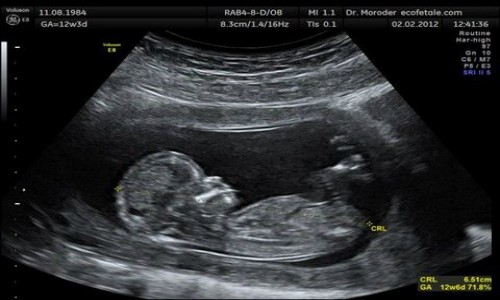

Η έγκυος μπροστά στα διλήμματα της έκτρωσης